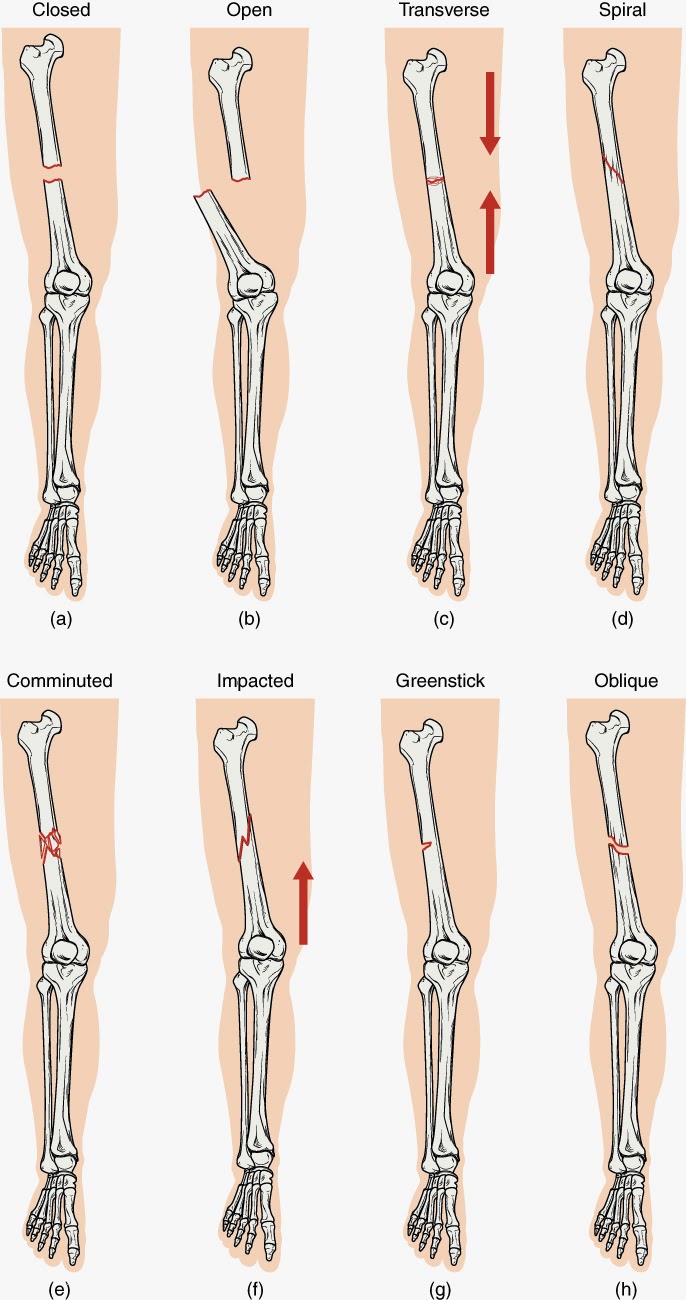

Jenis Dan Kategori Tulang Patah

Jenis Dan Kategori Tulang Patah

Topik 4 sains sukan

Topik 4 sains sukan

Fraktur - Jenis û Penyebab dan Pengobatan - IDN Medis

Fraktur - Jenis û Penyebab dan Pengobatan - IDN Medis

Bab 5 luka & patah

Bab 5 luka & patah

Ini yang Dimaksud dengan Fraktur Tulang

Ini yang Dimaksud dengan Fraktur Tulang